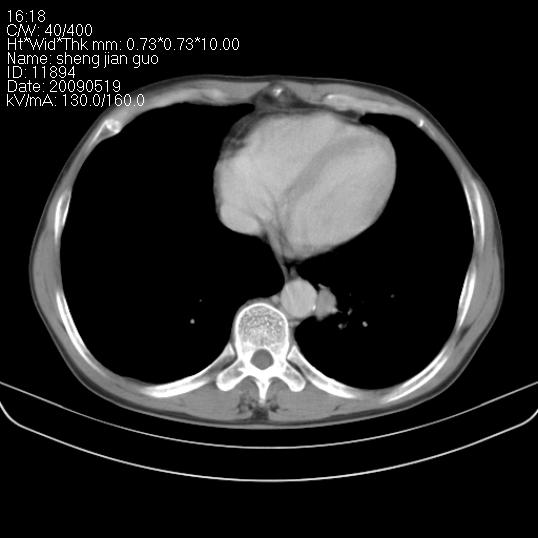

以下是引用zjzjr在2009-5-19 17:25:00的发言:[br]支持楼主考虑,另左肺下叶阻塞性炎症。

以下是引用zhao_bin2008在2009-5-19 17:48:00的发言:[br]支持左肺下叶周围型肺癌并阻塞性肺炎。

以下是引用zsl6918在2009-5-20 7:10:00的发言:[br]左侧中心型肺癌!